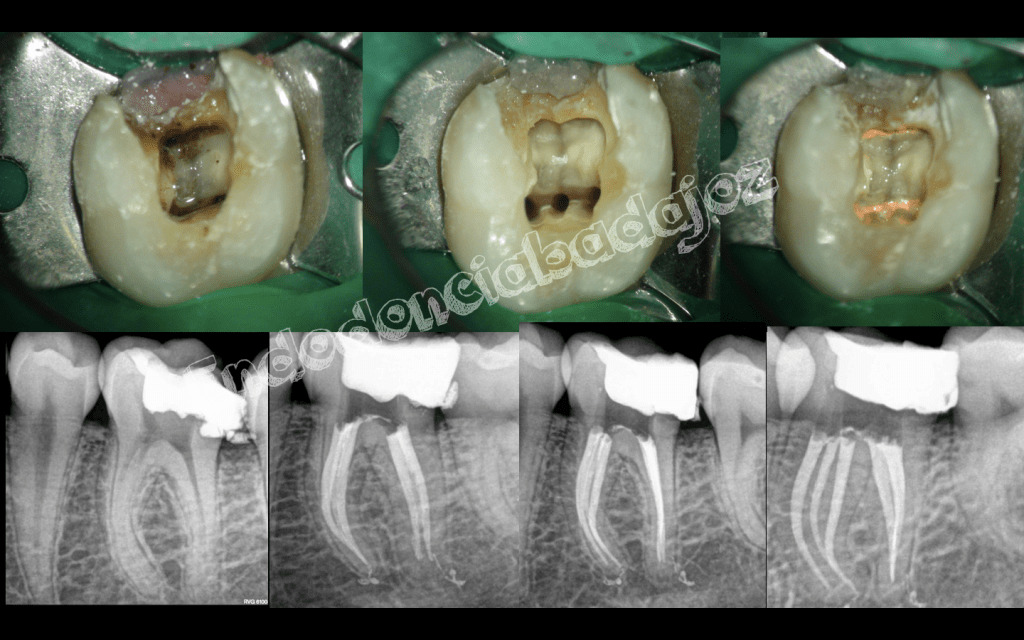

Después de una temporada sin postear ningún caso, hoy me levanté con ganas de publicar alguno, se trata de cinco casos, a mi juicio, interesantes, cuatro endodoncias de molares inferiores con anatomías complicadas y un retratamiento de un molar superior . Espero que os gusten.

3. Hola, te quería preguntar si es normal que se vea como un hueco entre la obturación y las raíces en casa na radiografía de una endodoncia.

• Hola Mariano, en una obturación definitiva hay que minimizar los gaps , pero esto tratamientos son con una obturación provisional, Por lo que esa interfase es telón para que le referidos pueda eliminar la obturación provisional. Un saludo